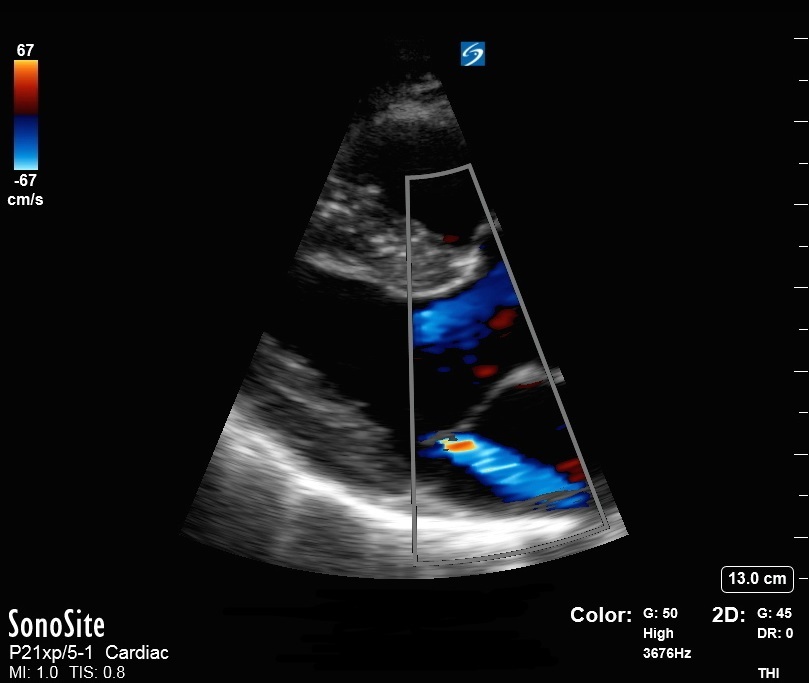

心臓Parasternal Long Axis (PLAX)僧帽弁閉鎖不全症画像